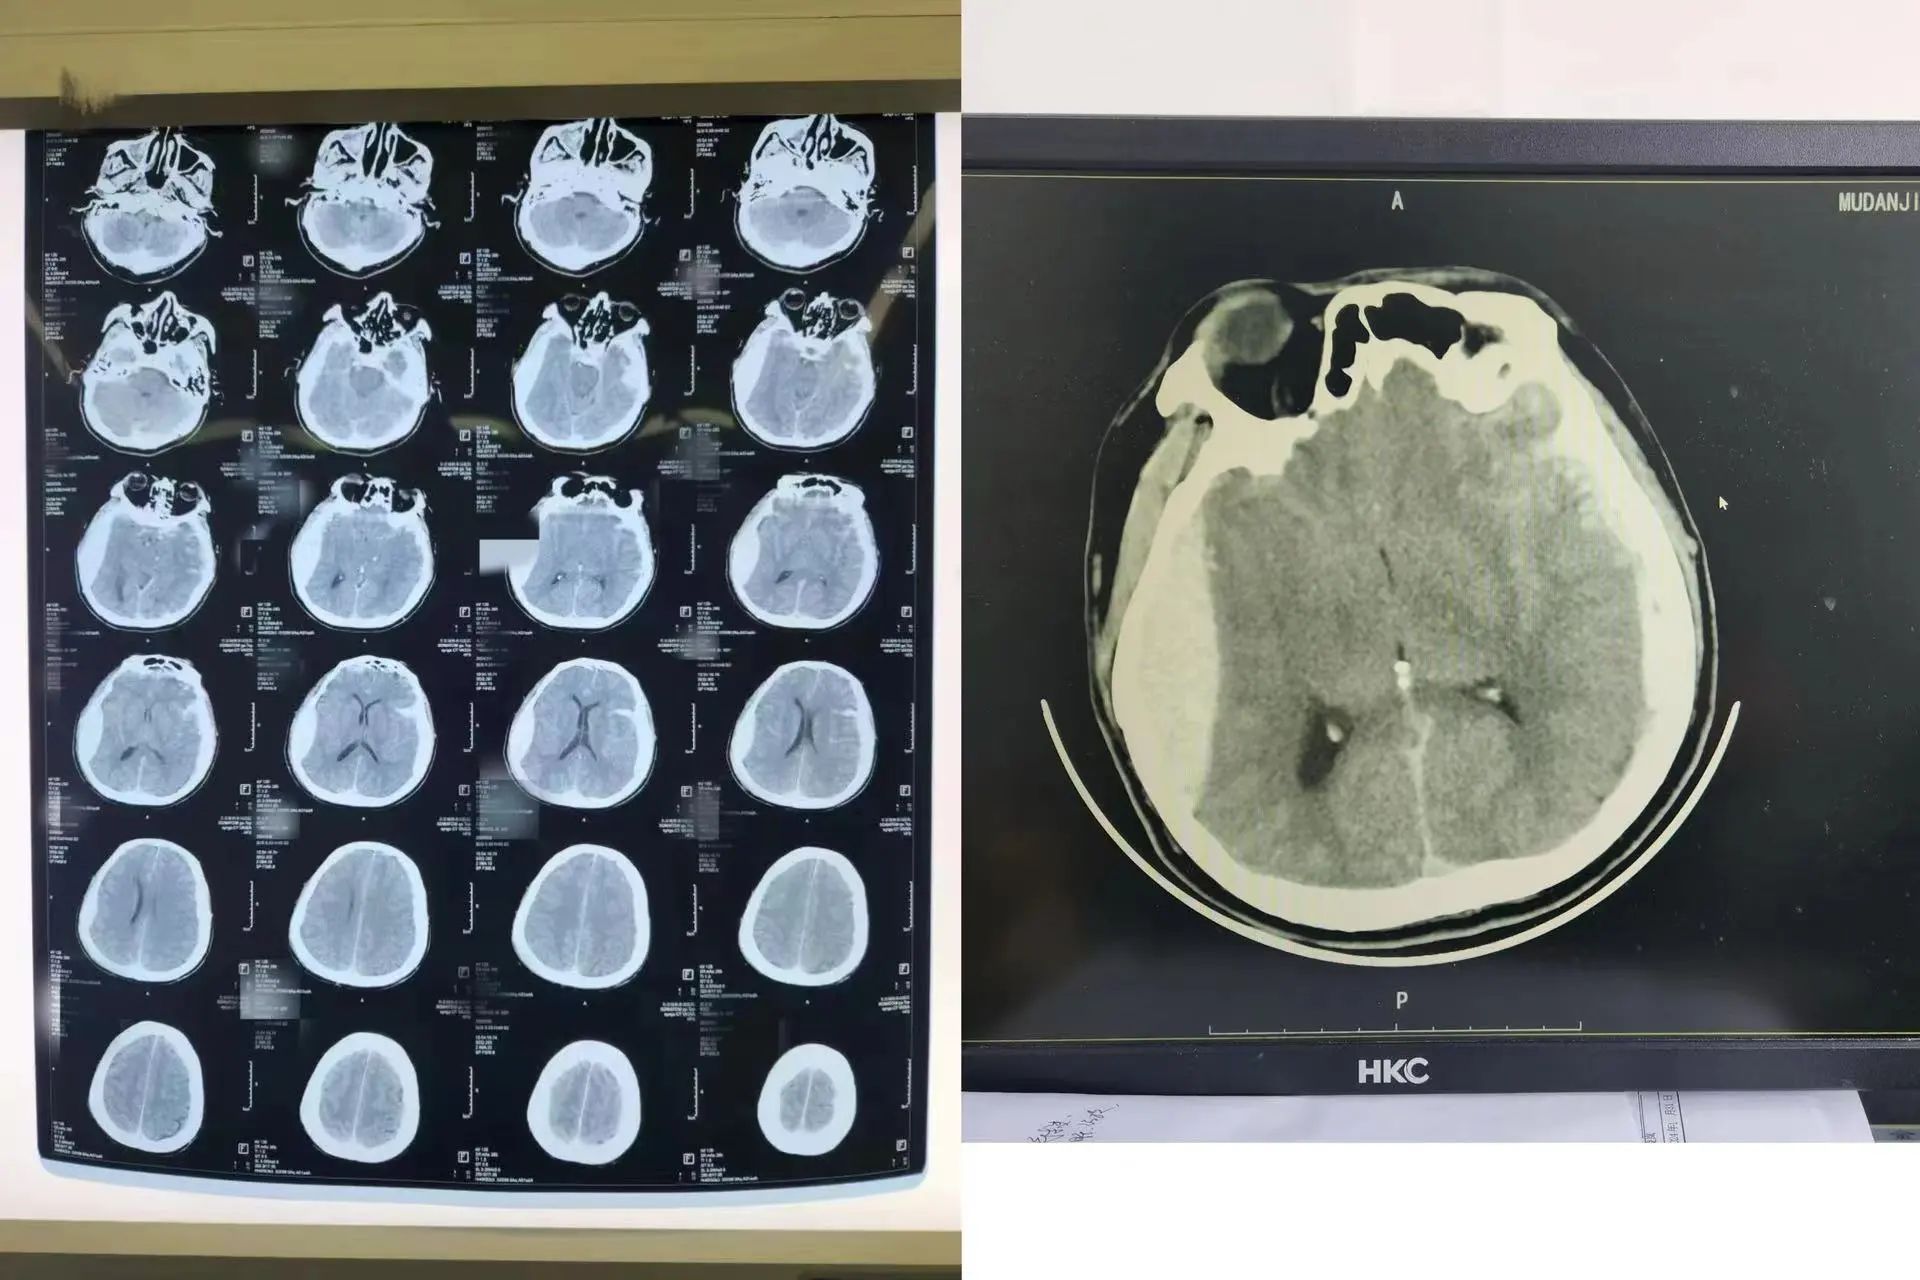

2月9日,正当大家沉浸在除夕的喜庆中时,牡丹江林业中心医院神经外科的电话铃声突然响起,“准备床位,一个急诊脑出血需要马上手术”。医护人员迅速按部就班,与急诊科交接患者后,护理组立即给予吸氧床边监护生命体征,采集标本头皮备皮,查体询问病情。原来,患者在除夕上午不慎摔倒,右枕部着地,意识不清,急诊送至医院。随后,神经外科王宏涛副主任医师立即组织术前抢救处置,并向家属交代病情:CT显示患者重度颅脑损伤、急性创伤性右侧硬膜下血肿、广泛脑挫裂伤、颅骨骨折。患者病情危重,只有立即手术清除血肿才能挽救患者生命。

在征得患者家属同意后,科室人员立即协调检验科、影像科为患者加急完善术前检查,与此同时迅速联系麻醉科、手术室,确保术前各项准备衔接得当,不浪费一分一秒。很快患者被推进手术室,王宏涛主刀为患者行开颅血肿清除加去骨瓣减压术。因患者颅脑损伤严重,术中多次出现血压不稳,波动很大,麻醉师凭借丰富急救经验使患者血压逐渐恢复正常。经过4个多小时的精细操作,血肿被清除,手术顺利完成。患者生命体征稳定,转入ICU留观并于2月14日转回神经外科继续治疗。